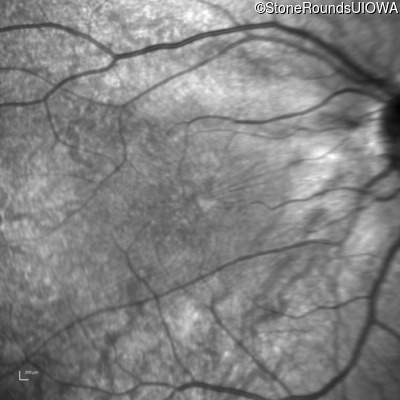

Infrared Fundus Photograph - Right - 20/50 -1

Exemplar